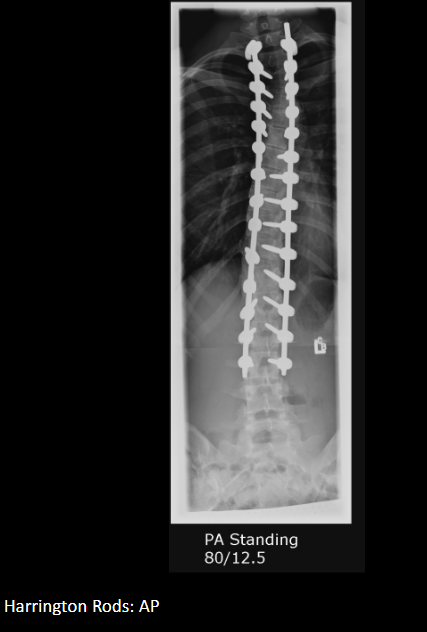

Two common surgical implants for scoliosis.

Harrington rods; Dwyer screws/wires.